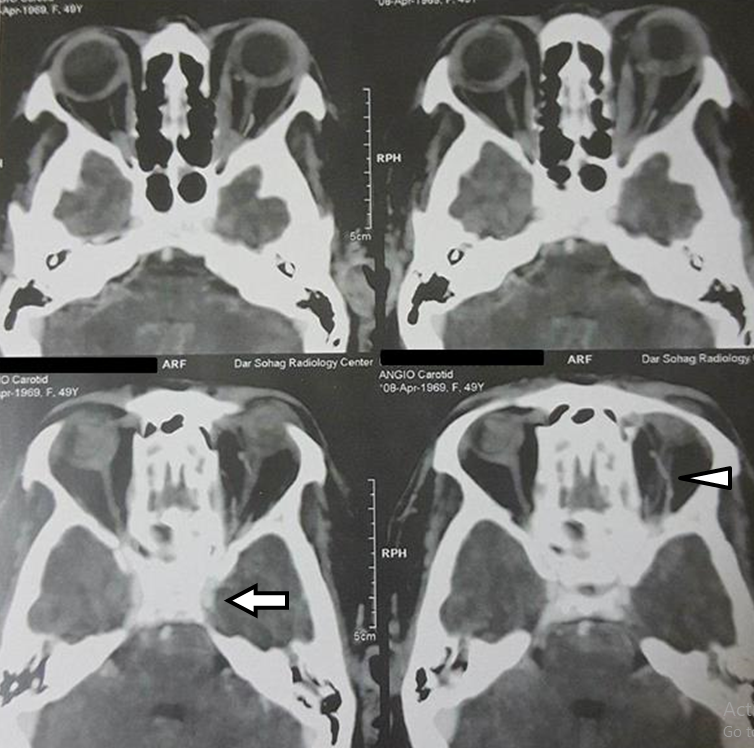

Computed tomography angiography (CT-A) was done (Figure 2 [Fig. 2]) with positive findings. Images showed minute small vessels (fistulas) around the early opacified left cavernous sinus with a dilated superior ophthalmic vein.

Figure 2: Minute small vessels around the early opacified left cavernous sinus (arrow) with dilated superior ophthalmic vein (arrow head)